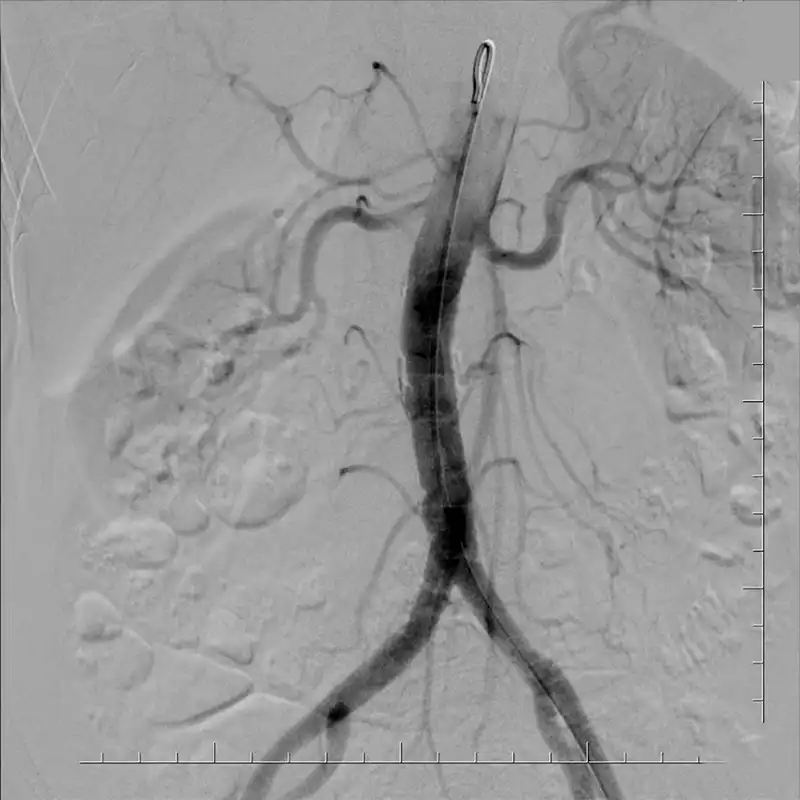

Expand the capabilities of limited R&F room space with Canon Medical Systems’ Ultimax-i, making advanced imaging technology and diverse multipurpose system performance truly attainable. Efficient installation opens up workflow space, allowing for more complex procedures—without breaking down walls.

Angiography, fluoroscopy, and radiography all together to increase the capabilities of imaging within an R&F space.